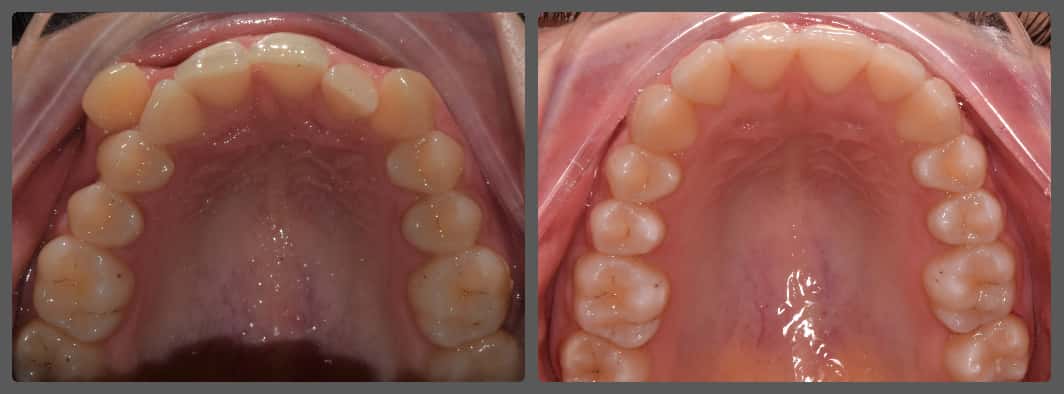

Karolina és szülei fogszabályozási konzultációra érkeztek hozzám. Fő panaszuk a felső torlódása és az elülső nyitottharapás volt. A diagnosztika után egyértelművé vált, hogy Karolina nyitottharapását egyszerű módon is korrigálni lehet, pusztán az elülső fogak lefelé mozgatására van szükségünk. A kezelés során Pitts21 önligírozó fogszabályzó készüléket alkalmaztunk. A nyitottharapás zárását intermaxilláris gumhúzással kezdtük el. Mivel Karolinának egy rossz szokása, nyelvlökéses nyelése is volt, ezért logopédushoz irányítottam a probléma megoldására, valamint a leszokás segítésére nyelvlökést gátló tüskéket ragasztottam a felső metszőfogaira (bocsánat😊). A kezelés 1 év 3 hónapig tartott, úgy gondolom, hogy nagyon rövid idő alatt sikerült igazán gyönyörű végeredményt elérnünk!